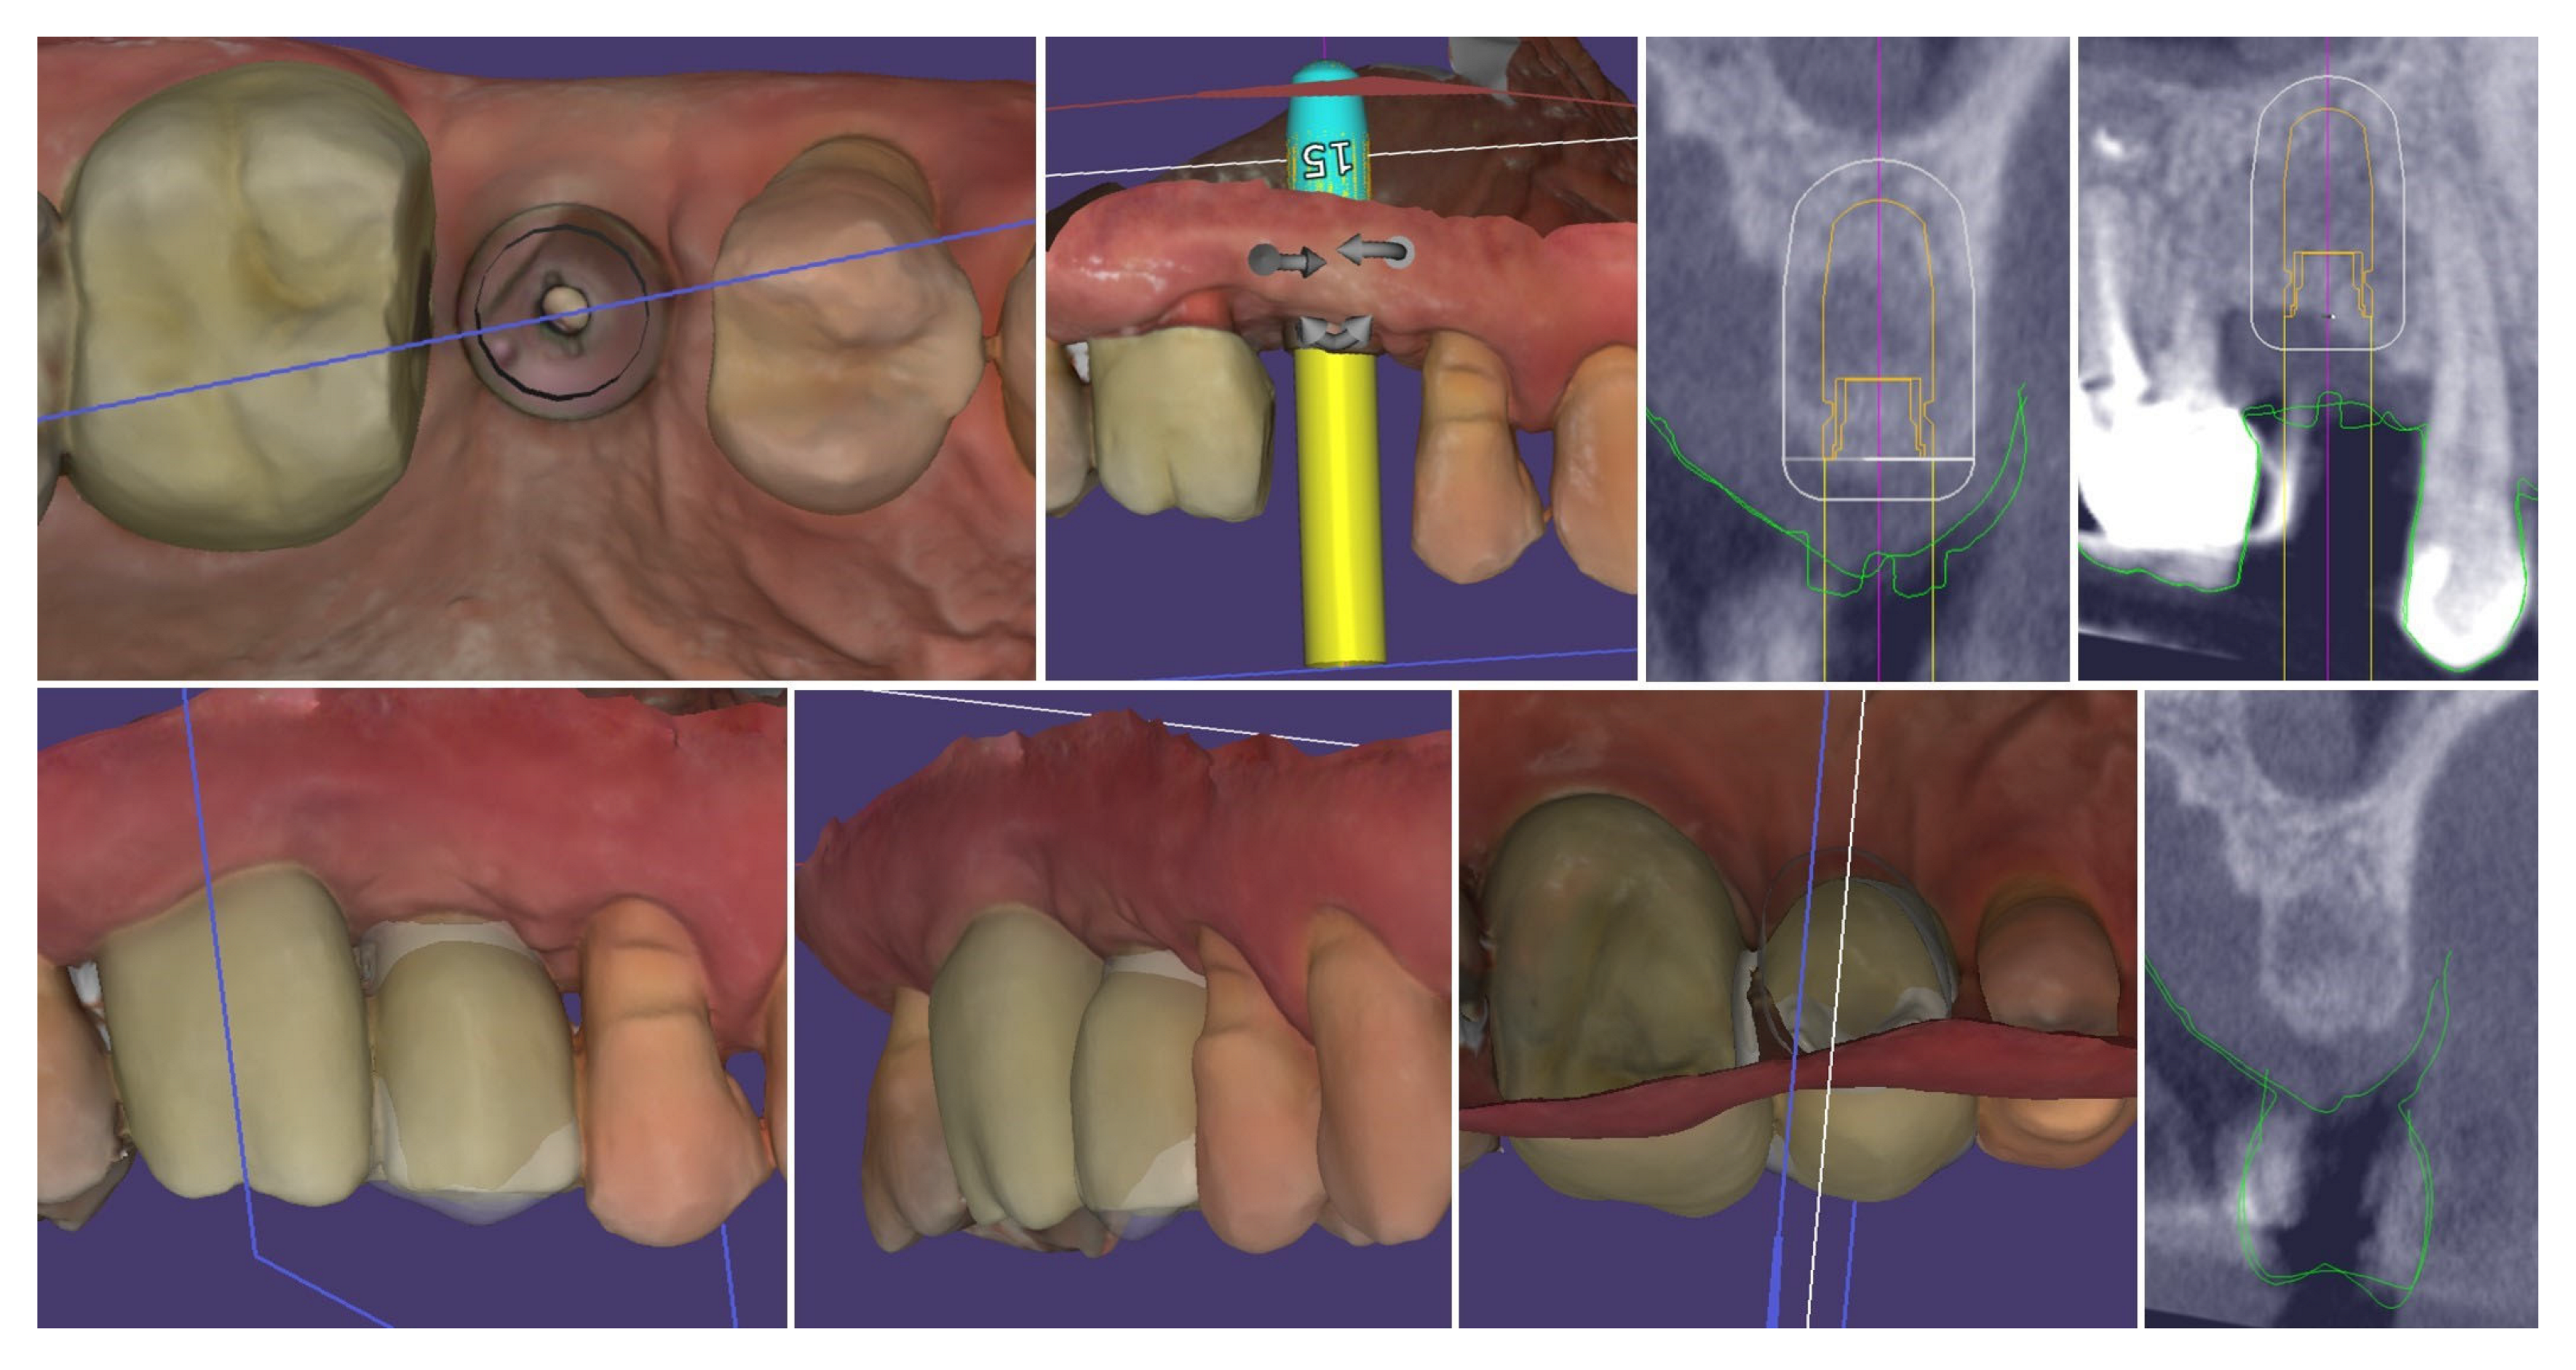

Digital planning of the dental implant was performed. It was determined that there was sufficient crestal bone volume to place the implant in the most appropriate prosthetically oriented position, for which a surgical guide was prepared for fully guided implantation (Figure 5).

Figure 5.

Digital planning of the dental implant.

The performed measurements showed adequate soft tissue dimension (≥3.5 mm) for stable peri-implant tissues crestally, 4.3 mm, and palatally, 5.4 mm, but at the buccal site, a pronounced volume deficiency was detected (2.3 mm soft tissue thickness), for which a soft tissue augmentation procedure was planned (Figure 6).

Figure 6.

Soft tissue dimensions analysis.

Figure 22 demonstrates the capabilities of the modern dental technology to assist the clinician in achieving accurate and reproducible results. The top row presents the congruence of the implant position with digital planning, while on the bottom row, the similarity between the prosthetic planning and the actual final crown is presented.

Figure 22.

Congruence of the implant position with digital planning and of the prosthetic planning with the final crown.